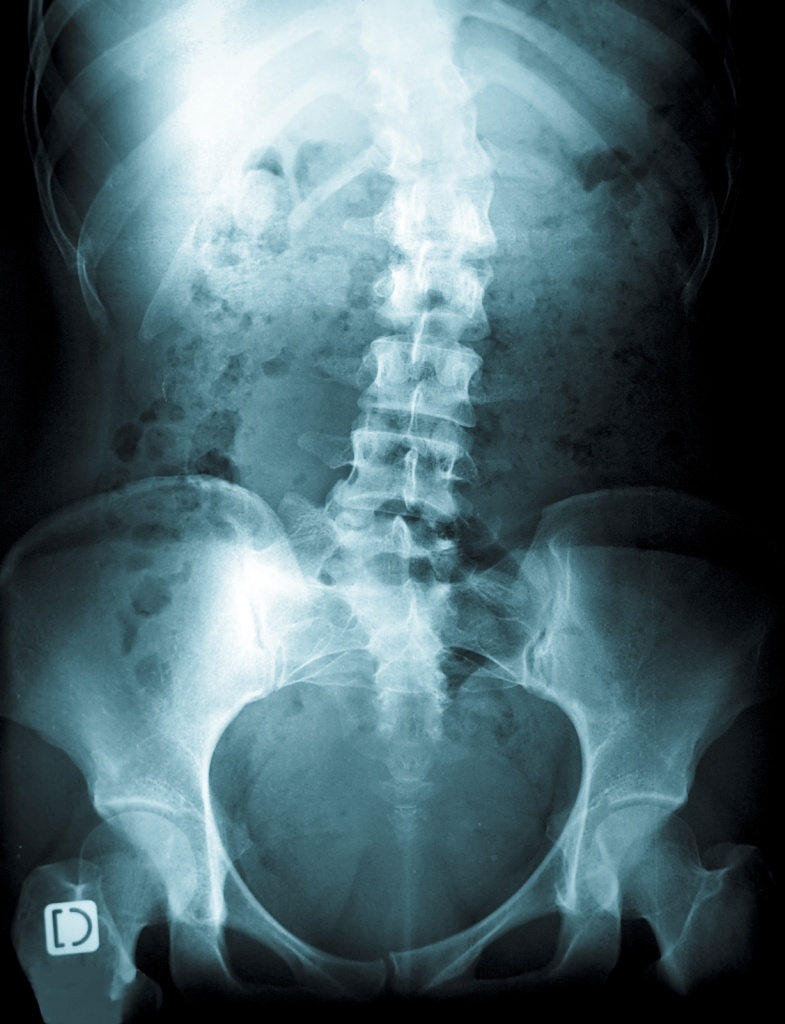

Рентгенограмма позвоночника при сколиозе

Сколиоз у детей. Стойкая деформация позвоночного столба, характеризующаяся его боковым отклонением и торсией. Сколиоз у детей сопровождается асимметричным положением надплечий, лопаток и других костных ориентиров, перекосом таза, деформацией грудной клетки, нарушениями со стороны внутренних органов. Для диагностики сколиоза у детей выполняются полипозиционные рентгенограммы позвоночника с расчетом величины искривления. Консервативное лечение сколиоза у детей включает ортопедический режим, массаж, корригирующую гимнастику, физиотерапию, ношение ортопедического корсета; по показаниям производится хирургическая коррекция сколиоза.

Раннее выявление сколиоза – важнейшая задача диспансерных осмотров детей дошкольного и школьного возраста педиатром, детским хирургом, неврологом, детским ортопедом. Для правильной оценки осанки необходимо последовательное обследование ребенка в положении стоя (спереди, сбоку, сзади), сидя и лежа. При этом обращают внимание на высоту надплечий, асимметрию кожных складок, лопаток, таза, наличие реберного горба и другие признаки сколиоза у детей. Степень искривления позвоночника в градусах определяют с помощью сколиозометра. Выявление отклонения позвоночника более чем на 5-7°, является основанием для проведения рентгенографии ребенку.

Рентгенография позвоночника выполняется в положении стоя и лежа в 2-х проекциях. На основании полученных спондилограмм производится расчет величины искривления по методике Фергюссона или Кобба, определение индекса стабильности позвоночника. Для более детального обследования интересующего отдела позвоночника может применяться рентгеновская томография, MРТ или КТ позвоночника, миелография. Для обследования и динамического наблюдения детей предпочтительнее применять нелучевые методы исследования, например, компьютерную оптическую топографию. Обязательным компонентом диагностики сколиоза у детей является фотографирование ребенка с различных точек на всех этапах наблюдения.